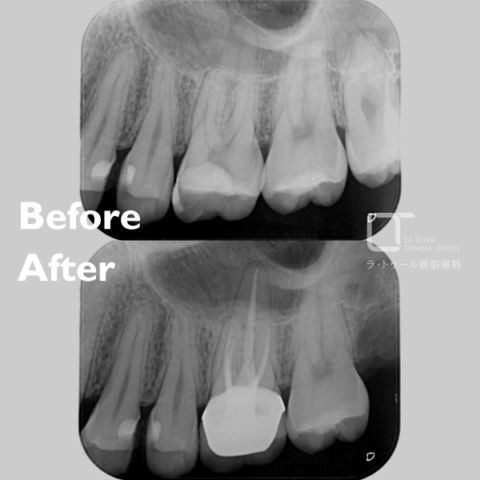

私はこれまでの勤務先医院、海外の研修会などで様々な歯科医療の勉強をしてまいりました。特に先進のマイクロスコープを用いた治療は、World basicになっておりますが、当院では4台導入しています。 歯科医療においては、根管治療は自然歯を残すための最後の砦と言われております。患者様の理解もなく、勝手に歯を抜かれたなどの多く耳にしますが、そのような事が起こらないために専門かつ先進の技術を活かし、患者様の健康へ貢献してまいります。 また、当院ではマイクロスコープの動画を用いて高倍率での動画説明を全ての治療で行うことでより細かな情報共有を実現することが可能となりました。 このように専門かつ先進の技術を駆使して、患者様のお口の健康から全身の健康、ひいては健康寿命の延伸に寄与してまいります。